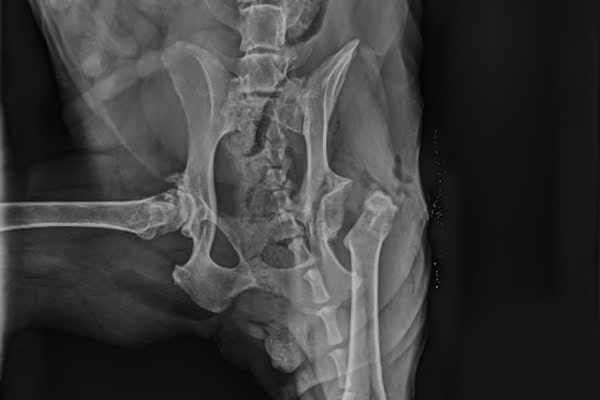

A number of conformational abnormalities make up hip dysplasia in dogs, including:

- A shallow acetabulum

- A flattened femoral head

- A thick femoral neck (the neck of the femur connects the head to the long part of the bone).

These issues can often be seen on X-rays of the hips.